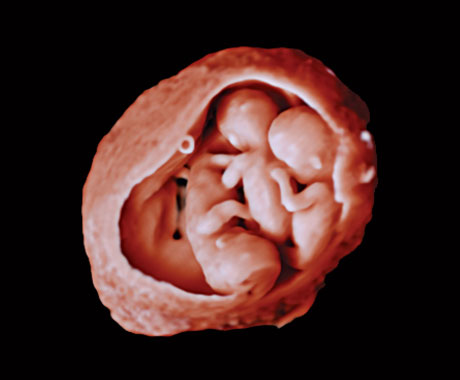

En este vídeo, el Dr. Michael Ruma presenta el transductor V9-2 para ultrasonidos 3D de Philips. El V9-2 es el primer transductor mecánico PureWave para ultrasonidos 3D de la división de ultrasonidos de Philips específico para obstetricia/ginecología y ofrece una extraordinaria calidad de imagen y un diseño ergonómico avanzado. El V9-2 está especialmente indicado para la adquisición de imágenes 2D, 3D y 4D para exploraciones obstétricas del primer, segundo y tercer trimestre.

Combinar el nuevo transductor V9-2 con el sistema de ultrasonidos de alta gama EPIQ Elite ofrece una adquisición de imágenes superior de obstetricia/ginecología:

Herramientas de visualización obstétrica avanzadas para una imagen fetal realista.